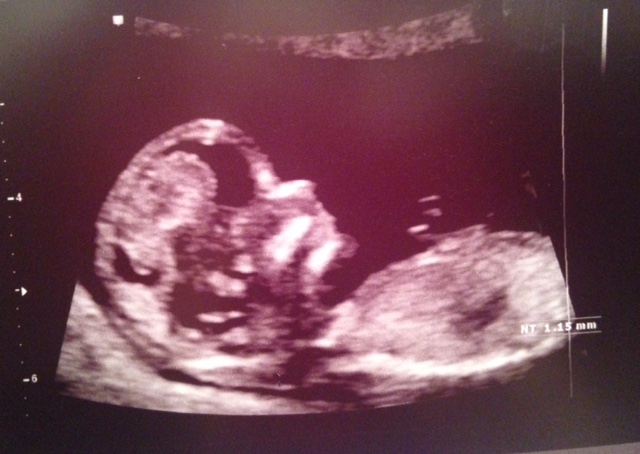

Our NT scan today revealed what the tech said was the most stubborn fetus he's tried to measure in some time. Got a picture with the tips of all 5 fingers up by their face. 12w4d, heart rate of 153 (I think).